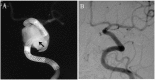

Case description: We report on a 63-year-old male who had a large internal carotid artery cavernous segment aneurysm. Treatment with PED resulted in complete occlusion of the aneurysm. However, follow-up angiography at four years revealed recurrence of the aneurysm due to disconnection of the two PEDs placed in telescoping fashion.